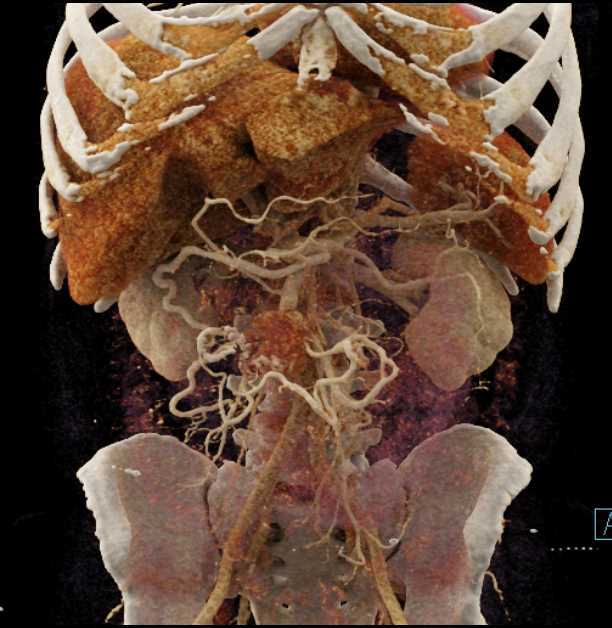

Carcinoid Tumor with Desmoplastic Reaction